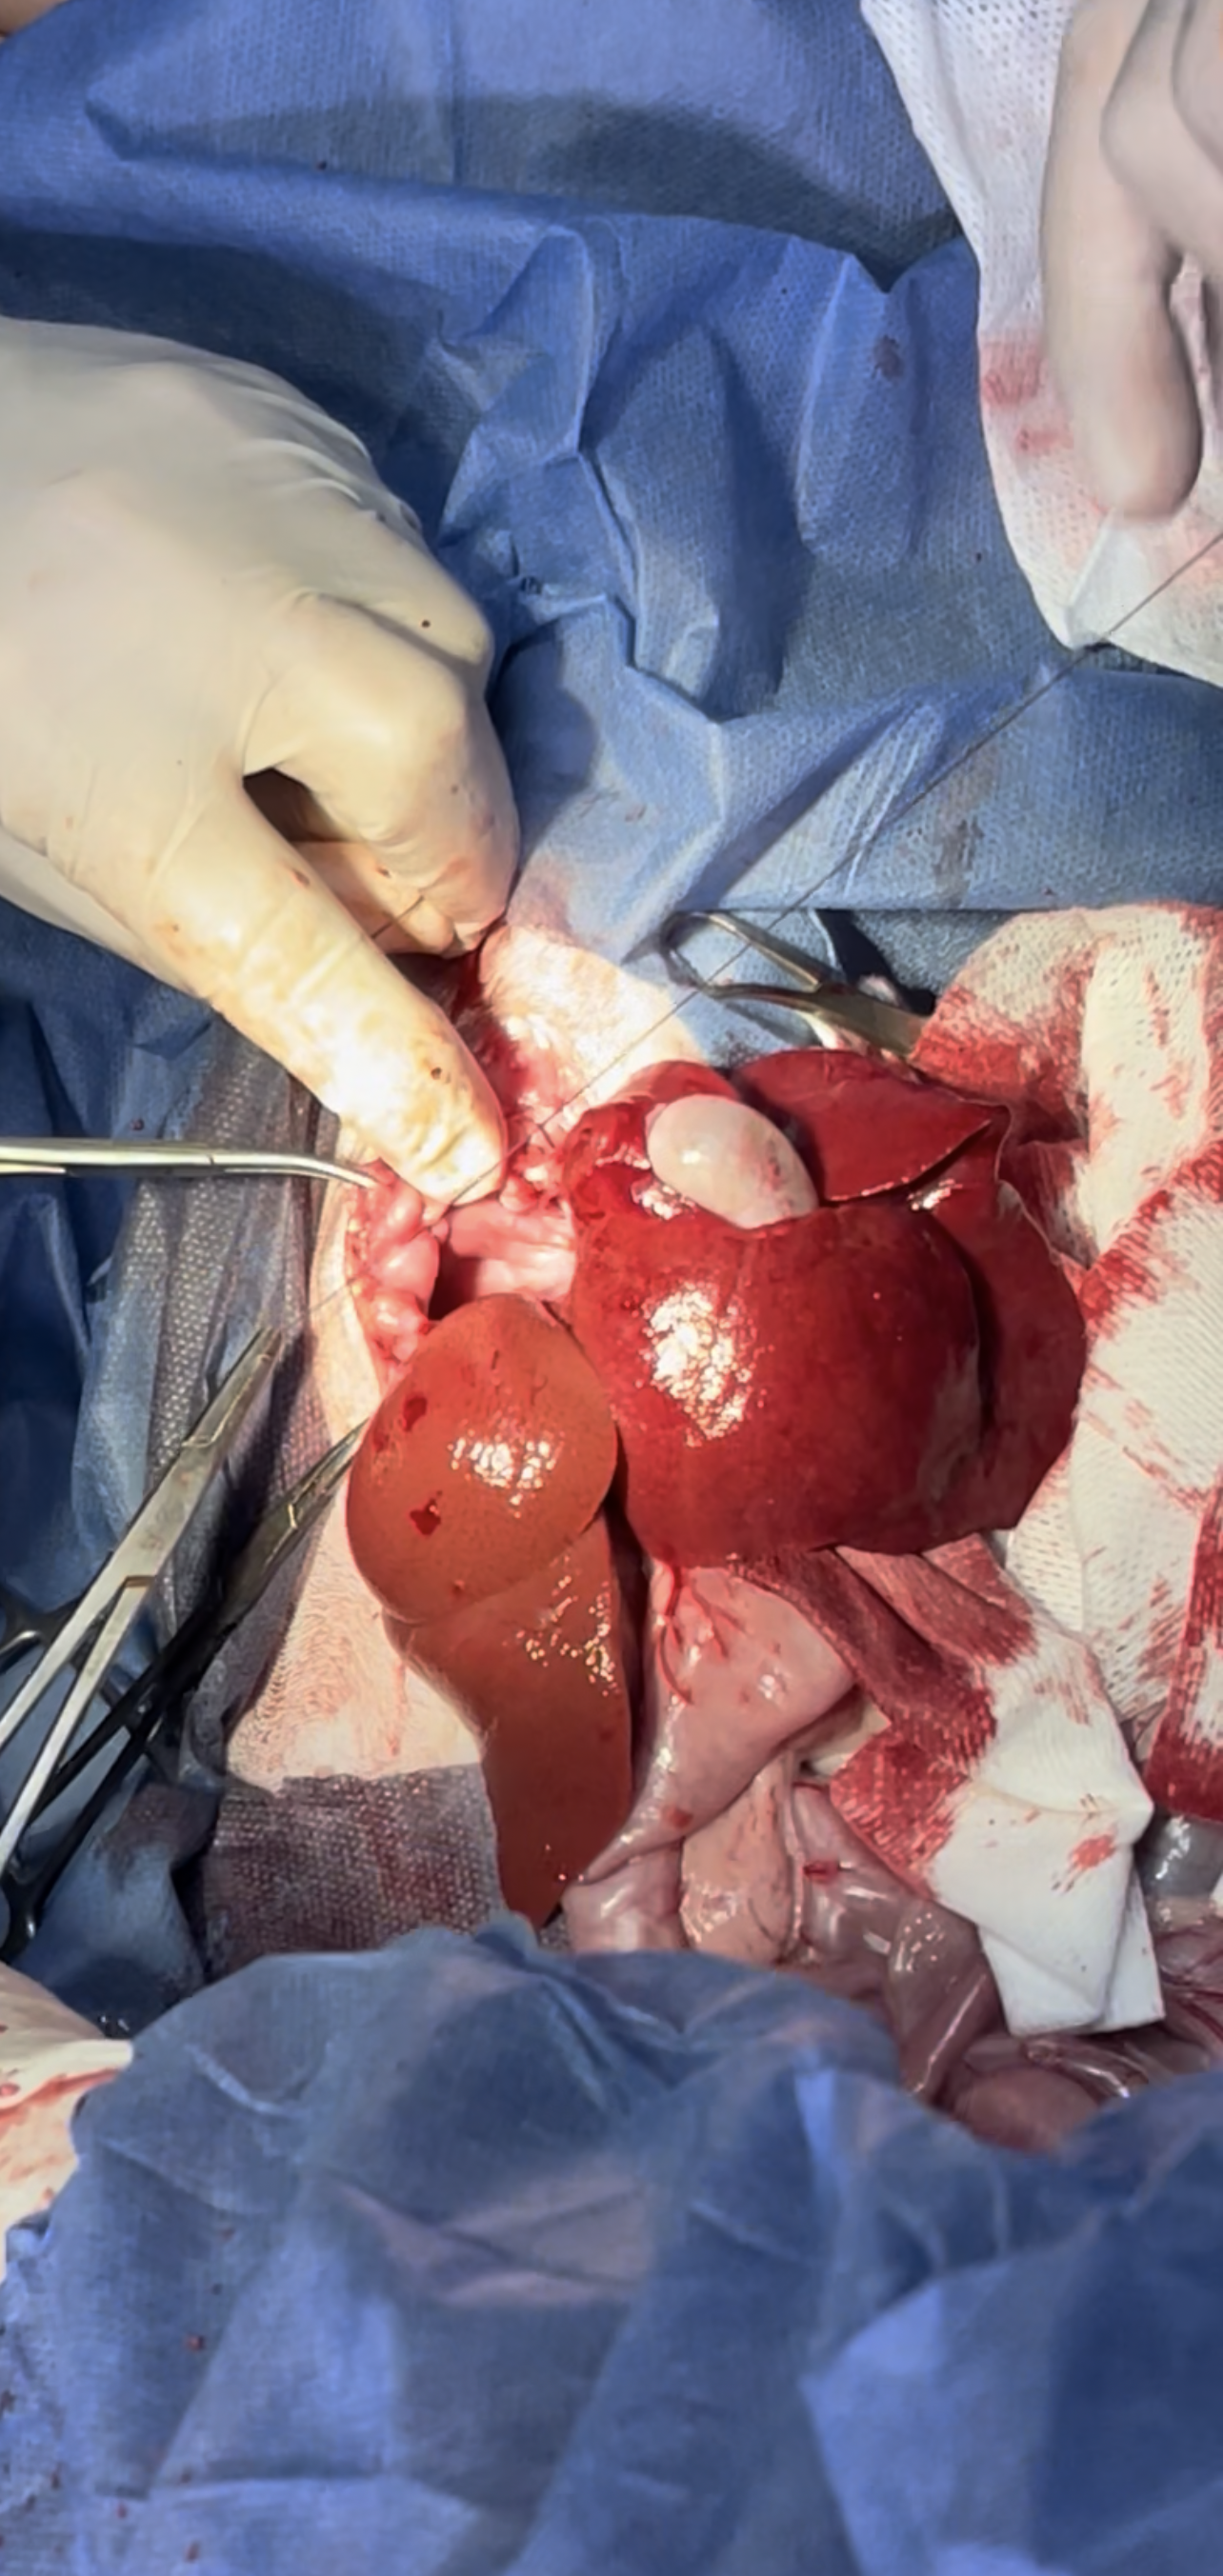

Stomach and intestines exteriorized and liver can be seen inside the thoracic cavity

Liver is exteriorized

Hernia is sutured with the tube passing through to extract the remaining air

3 way stop catheter is used for faster air extraction

tube is removed and purse string around the tube closed immediately